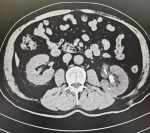

直腸癌術(shù)后半月陰道竟溢出糞便樣物,如何診治 現(xiàn)病史【一般資料】 女性,59,農(nóng)民 【主訴】 直腸癌術(shù)后半月,陰道溢出糞便樣物3天。 【現(xiàn)病史】 患者及家屬訴緣于半月前因直腸癌行手術(shù)治療,術(shù)后恢復(fù)良好,正常排氣、排便。3天前無(wú)明確誘因陰道溢出糞便樣物,質(zhì)稀,每次量不多,約十毫升左右,無(wú)腹痛,無(wú)黏液膿性便,無(wú)鮮血便,無(wú)發(fā)冷、發(fā)熱,無(wú)惡心嘔吐,無(wú)心慌、氣